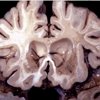

La Adrenoleucodistrofia no es una enfermedad cotidiana, pero puede ocurrirle a cualquiera. Adrián es uno de los afectados por esta enfermedad y necesita ser operado de urgencia.

¿Y si te dijeran después de seis años acudiendo a tu centro hospitalario que padeces una enfermedad que puede acabar contigo a lo largo de dos años? ¿Cuál sería nuestra actitud? Esto es lo que les ha sucedido a los padres de Abraham, un niño de seis años oriundo de Málaga, que aunque lo habían tratado desde los seis meses en la especialidad de Neurología Infantil de su hospital, no fue hasta el año pasado cuando le diagnosticaron Adrenoleucodistrofia severa infantil, un problema congénito que le llevara a un fallecimiento precoz sino se realiza un trasplante de médula ósea con urgencia en Minnesota (Estados Unidos). Ya que el Ministerio de Sanidad no puede cubrir unos gastos tan costosos y no existe tal operación en territorio nacional, la familia y otros colaboradores están creando campañas para la participación de la ciudadanía, pues necesitan recaudar la friolera cantidad de un millón de dólares (751.000€) y sus humildes retribuciones mensuales no les permiten hacerse cargo de pagar tan alta cuantía.